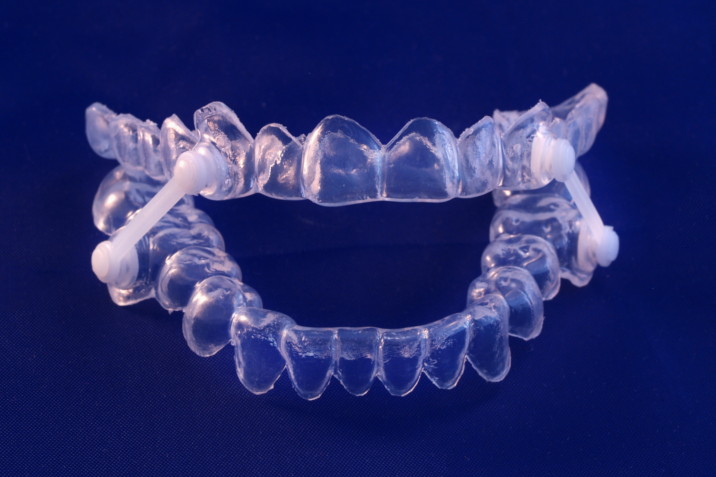

Bruxismoa eta Ferulak

Hortz higaduren prebentzioa. Hobe aurreikustea!!!

- Kirolerako aho-babeskia

- Deskargarako Ferula

- Artikulazioetako minarentzat Ferula (ATM)

Zurrungak eta Apneak

Orthoapneak

- Zurrungak saihestekoa

- Lo egitean arnasik gabe ez geratzeko

- Eguna logurez edo nekaturik ez igarotzeko